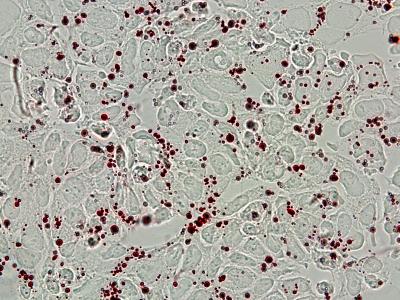

The molecule used by the researchers is no drug candidate; instead the finding is to be seen as a model that can inspire future cancer therapies. However, the researchers did find that the survival rate increased when they applied test treatments on mice with neuroblastoma. The study also led to a new discovery on what happens inside the cancer cell, where the treatment caused an accumulation of fat droplets, suggesting that the MYC proteins affect tumour cell metabolism and the normal breakdown of fatty acids.

"This is an original finding," says Professor Arsenian Henriksson. "It has not previously been observed that the inhibition of MYC affects tumour cells in this way. This does not only open new avenues for novel therapies for certain forms of cancer, but may also have implications for metabolic diseases, such as diabetes."

Publication: 'MYC inhibition induces metabolic changes leading to accumulation of lipid droplets in tumor cells', Hanna Zirath, Anna Frenzel, Ganna Oliynyk, Lova Segerström, Ulrica K. Westermark, Karin Larsson, Matilda Munksgaard Person, Kjell Hultenby, Janne Lehtiö, Christer Einvik, Sven Påhlman, Per Kogner, Per-Johan Jakobsson, and Marie Arsenian Henriksson, PNAS online 3-7 June 2013. EMBARGOED until 3 June 2013 at 3 pm US Eastern Time / 21:00 CET / 20:00 UK time.